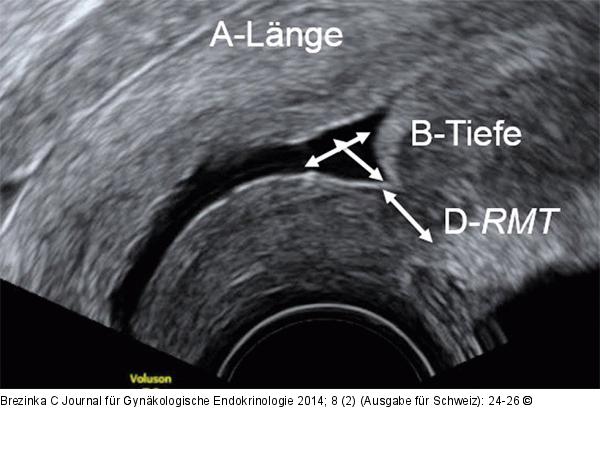

Abbildung 4: Gyn-Ultraschall Vergrößerung von Abbildung 3: Die Messung der einzelnen Strecken gelingt nicht immer so deutlich, sollte aber dennoch dokumentiert werden. |

Vergrößerung von Abbildung 3: Die Messung der einzelnen Strecken gelingt nicht immer so deutlich, sollte aber dennoch dokumentiert werden. |